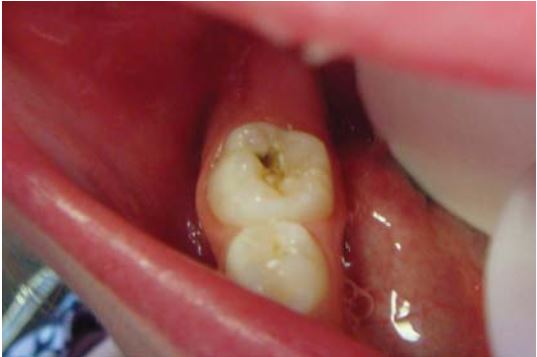

Mở rộng hố rãnh bằng mũi tròn #2 trước khi bơm sealant đôi khi được khuyến cáo để tăng bề mặt kết dính hoặc loại bỏ mô răng sâu (H9.6).

Trám răng ở trẻ thường được thực hiện trong vòng 5 phút hoặc ít hơn 5 phút và thường không cần gây tê hoặc đặt đê. Loại bỏ phần ngà sâu bằng mũi khoan tròn lớn với tay khoan chậm.

Có thể sử dụng cây nạo ngà, nhưng phải rất cẩn thận vì dễ có nguy cơ thủng vào buồng tủy khi lấy đi một lượng ngà lớn (H1.6).